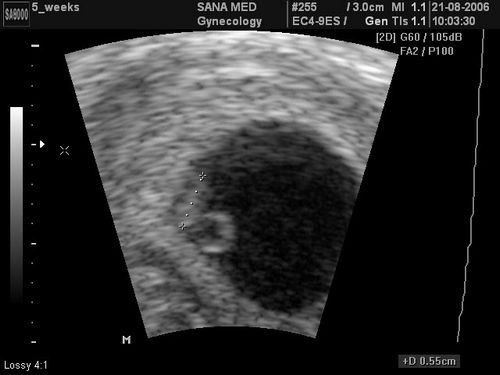

Саме тому більшість жінок відправляється на прийом до гінеколога. Але і тут не обійтися без спеціального обладнання. На другому тижні вагітності збільшення матки може ще не прощупується і лікар не скаже вам нічого певного з точною упевненістю. Тому, коли присутній вагітність два тижні, має сенс зробити фото УЗД. Тут результат не буде помилковим. Більшість жінок у цьому впевнені.

Але завдяки проведенню УЗД, на другому тижні вагітності лікар може побачити ймовірну загрозу викидня і якщо ця вагітність для жінки бажана і вона хоче її зберегти, то запобігти таку ймовірність. Справа в тому, що на терміні два тижні мимовільні викидні бувають у багатьох жінок. І найголовніше, що більшість з них навіть не підозрюють про те, що були вагітні. Зрив відбувається разом з початком регулярних місячних, і лише невеликі згустки крові можуть видати наявність вагітності, яка була перервана. Тому другий тиждень вагітності - це досить небезпечний термін, який триватиме аж до того моменту, коли настане десятий тиждень вагітності. Зроблене фото УЗД допоможе запобігти ймовірні ризики, але не всі і не завжди.

Крім того, коли настає другий тиждень вагітності, зроблене УЗД допоможе діагностувати позаматкову вагітність. Це патологія, яка унеможливлює не тільки розвиток ембріона, але і являє собою реальну загрозу для вагітних жінок. Тільки УЗД покаже цю проблему або спростує її існування. Своєчасна діагностика патології може стати запорукою порятунку вашого життя шляхом оперативного втручання.

Другий тиждень вагітності - особливий період. На цьому терміні більшість жінок дізнаються, що всередині них почала свій розвиток нове життя. На фото УЗД вже видно крихітний ембріон, розміром з маленьку піщинку. Це буде перше фото вашої майбутньої дитини, яке принесе вам радість і задоволення, особливо в тому випадку, коли вагітність довгоочікувана. Ваш організм тільки починає змінюватися, і поки зовні ви ще не помічаєте змін. Це час, коли вагітна жінка зможе усвідомити, що скоро вона стане матір'ю і звикнути до своєї нової ролі.